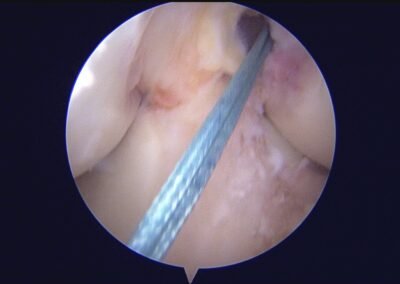

GalleryShoulder rotator cuff repair Meniscus root repair Meniscus repair Bankart repair for recurrent shoulder dislocation ACL reconstruction Machines Instruments